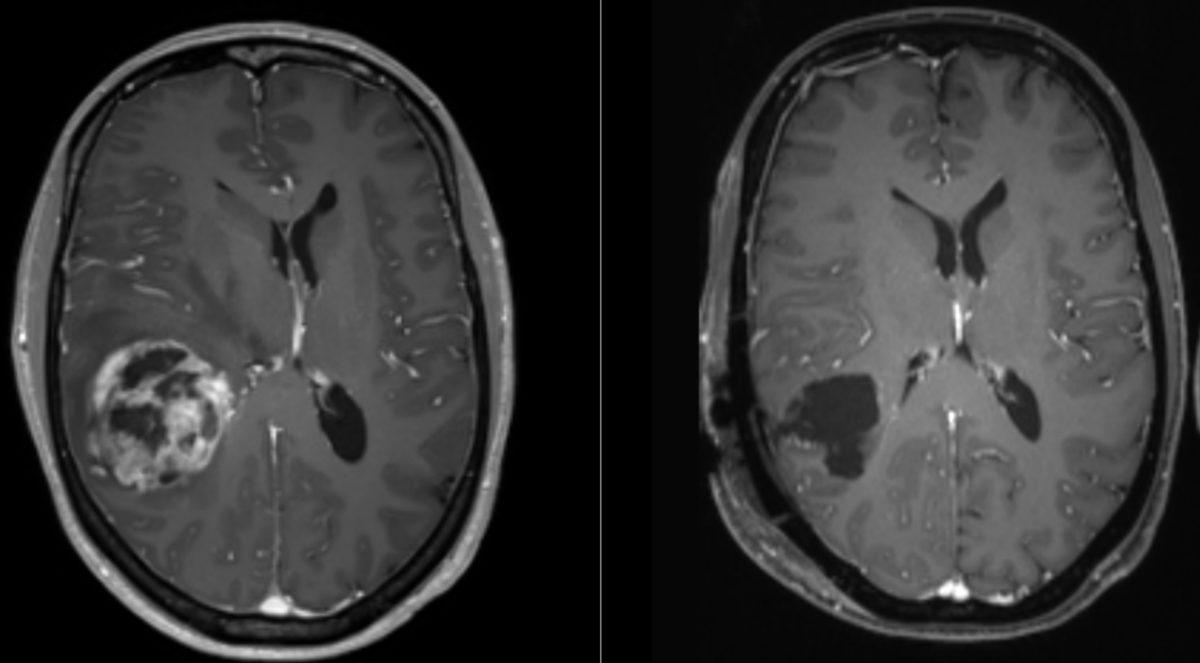

Glioblastoma, beyin kanseri türleri arasında en ölümcül türlerden biri olarak biliniyor. Bu hastalık ortaya çıktıktan sonra hastaların büyük kısmı 1-1,5 yıllık bir süreçte hayatını kaybediyor ve 5 yıldan uzun süre hayatta kalanların oranının ise sadece %7 olduğu belirtiliyor. Üstelik bu süreç boyunca hastalık baş ağrısı, hafıza kaybı, düşünme ve davranış değişiklikleri gibi belirtilere de sahip.

Şu anda kullanılan tedaviler arasında ameliyat, radyasyon ve kemoterapi yer alıyor. Bu yöntemler geçici çözümler sunuyor ve hastalığın kendisini değil semptomlarını tedavi ediyor. Vücut bu kanser hücrelerine karşı doğal bir savunma geliştiremiyor ve verilen ilaçlar da, kan beyin bariyerini genellikle aşamıyor.